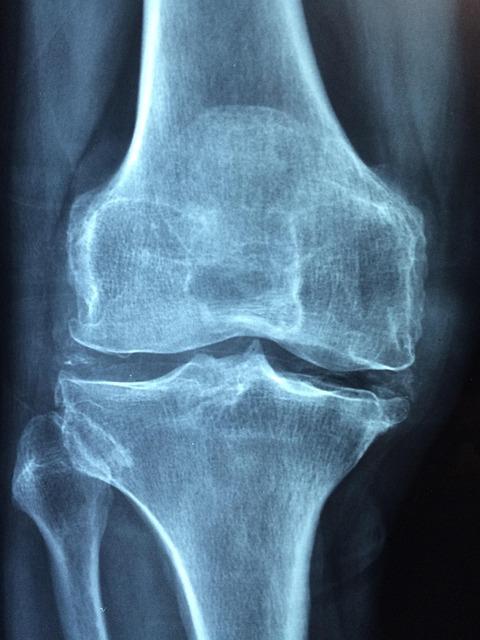

Evaluarea inițială se bazează pe o anamneză detaliată și un examen clinic orientat spre articulaţia afectată; investigaţiile imagistice, precum radiografia, ecografia sau RMN-ul, împreună cu analizele de laborator, pot oferi indicii despre prezenţa lichidului sinovial, gradul de inflamaţie şi posibile cauze (traumatice, inflamatorii sau infectioase). Aceste elemente, puse în context, pot ajuta la diferenţierea între sinovită şi alte afecţiuni articulare care pot avea simptome similare.